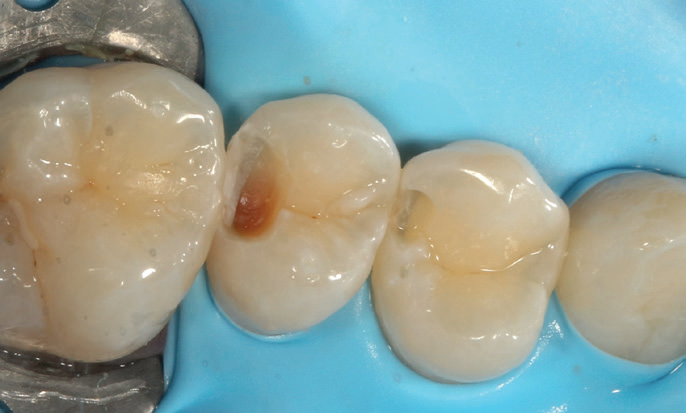

After removing the decay, I took several photos to help illustrate the cavity’s extent. I then placed a sectional matrix to ensure proper contact closure, as the cavity was large. After this, I applied Stela.

Figure 4: Distal caries removed UL5, distal fractured cleaner UL4